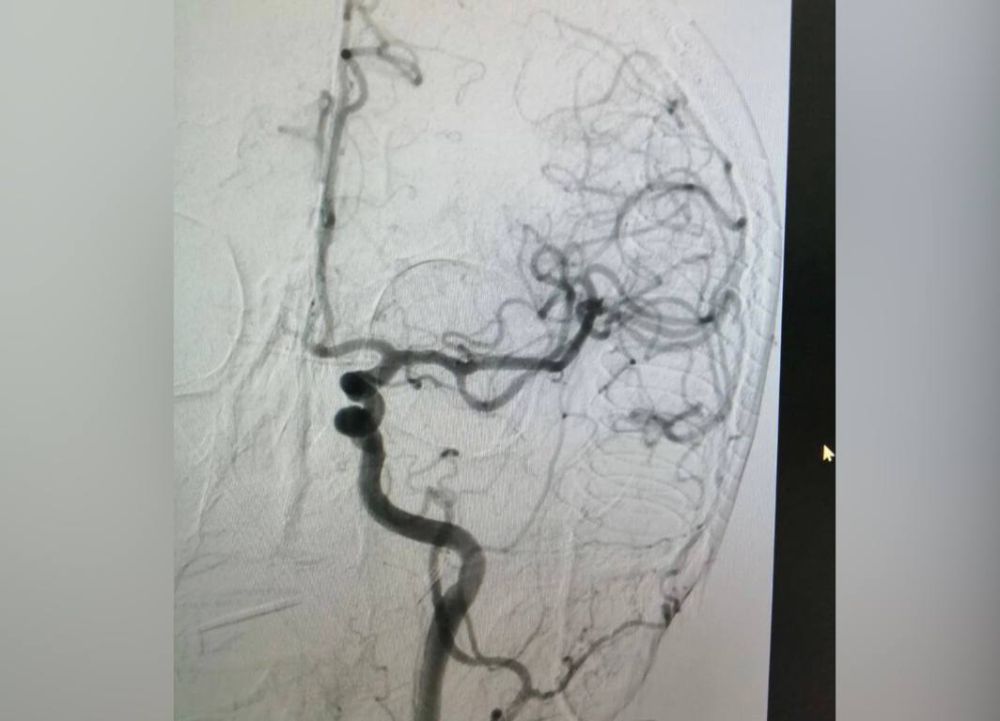

Снимок артерий. Фото: ГАУЗ «ГБ» г. Орска

Перед тем как начать операцию, хирурги убедились в том, что у пациента действительно закрыта крупная мозговая артерия. Именно ее нужно было открыть. Выяснить это удалось благодаря КТ. Пенсионеру было введено контрастное вещество, которое помогло определить наличие тромба.